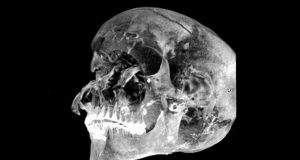

Peneliti Mengungkap Kematian Tragis Raja Mesir Kuno Seqenenre Taa II

Teknologi pemindaian modern mengungkap kisah di balik kematian seorang raja Mesir kuno yang menemui kematiannya dengan tragis. Dia adalah Raja Seqenenre Taa II. Memerintah...